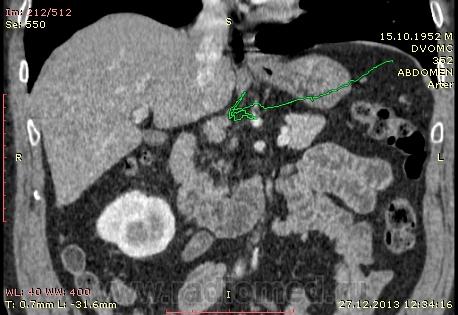

61 год. Рак желудка, в 2011 году субтотальная резекция. Жалоб нет. На вид здоровый, не худой, розоволицый мужик. На УЗИ нашли гиперэхогенное образование в VI сегменте печени 0.8 х 0.6 см. Рекомендовали КТ. Ну и вот: в печени в VI сегменте мелкий кальцинат...больше ничего страшного не вижу. В аорте куча мягких и "твердых" бляшек. Очень интересует Ваше мнение по поводу найденых, как мне кажется, достаточно крупных лимфоузлов...не похожи на метастатическое поражение?

Желудок резецирован по Б-II, лимфоузлы не увеличены. Подпеченочный аппендикс.

и в портальную фазу практически равны по плотности сосудам. Нормальные лимфоузлы всегда гиподенснее сосудов. Форма лимфоузлов может быть любой, и лишь округлость во всех реконструкциях может свидетельствовать о лимфаденопатии. Обычно паракавальный узел крупный и овально-округлый в короналах, но уплощенный на сагитталах, как в вашем случае - нормальный. Не всегда видны жировые ворота лимфоузла. При воспалительной лимфаденопатии узел может быть крупным, "набухшим", при сохранении жировых ворот. Округлый лимфоузел размерами даже меньше нормы в коротком поперечнике, но с патологическим накоплением контраста, считается измененным, и подозрителен на метастаз.

Для информации: симуляция паракавальной лимфаденопатии: